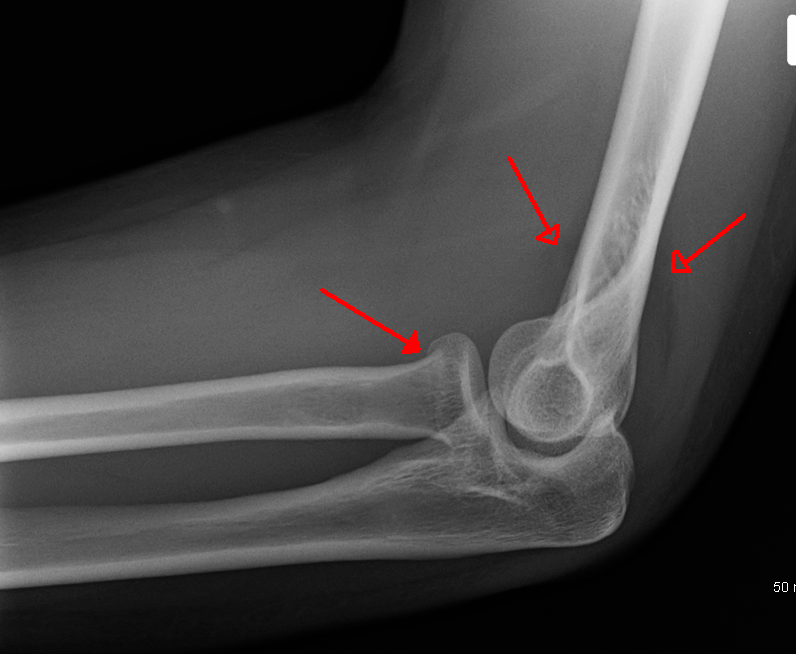

- 근위부 노뼈 골절: 팔꿈치 관절의 관절낭 내 골절은 팔꿈치에서 지방 패드의 변위를 나타내는 지방 패드 징후 또는 "돛 징후"를 유발한다.